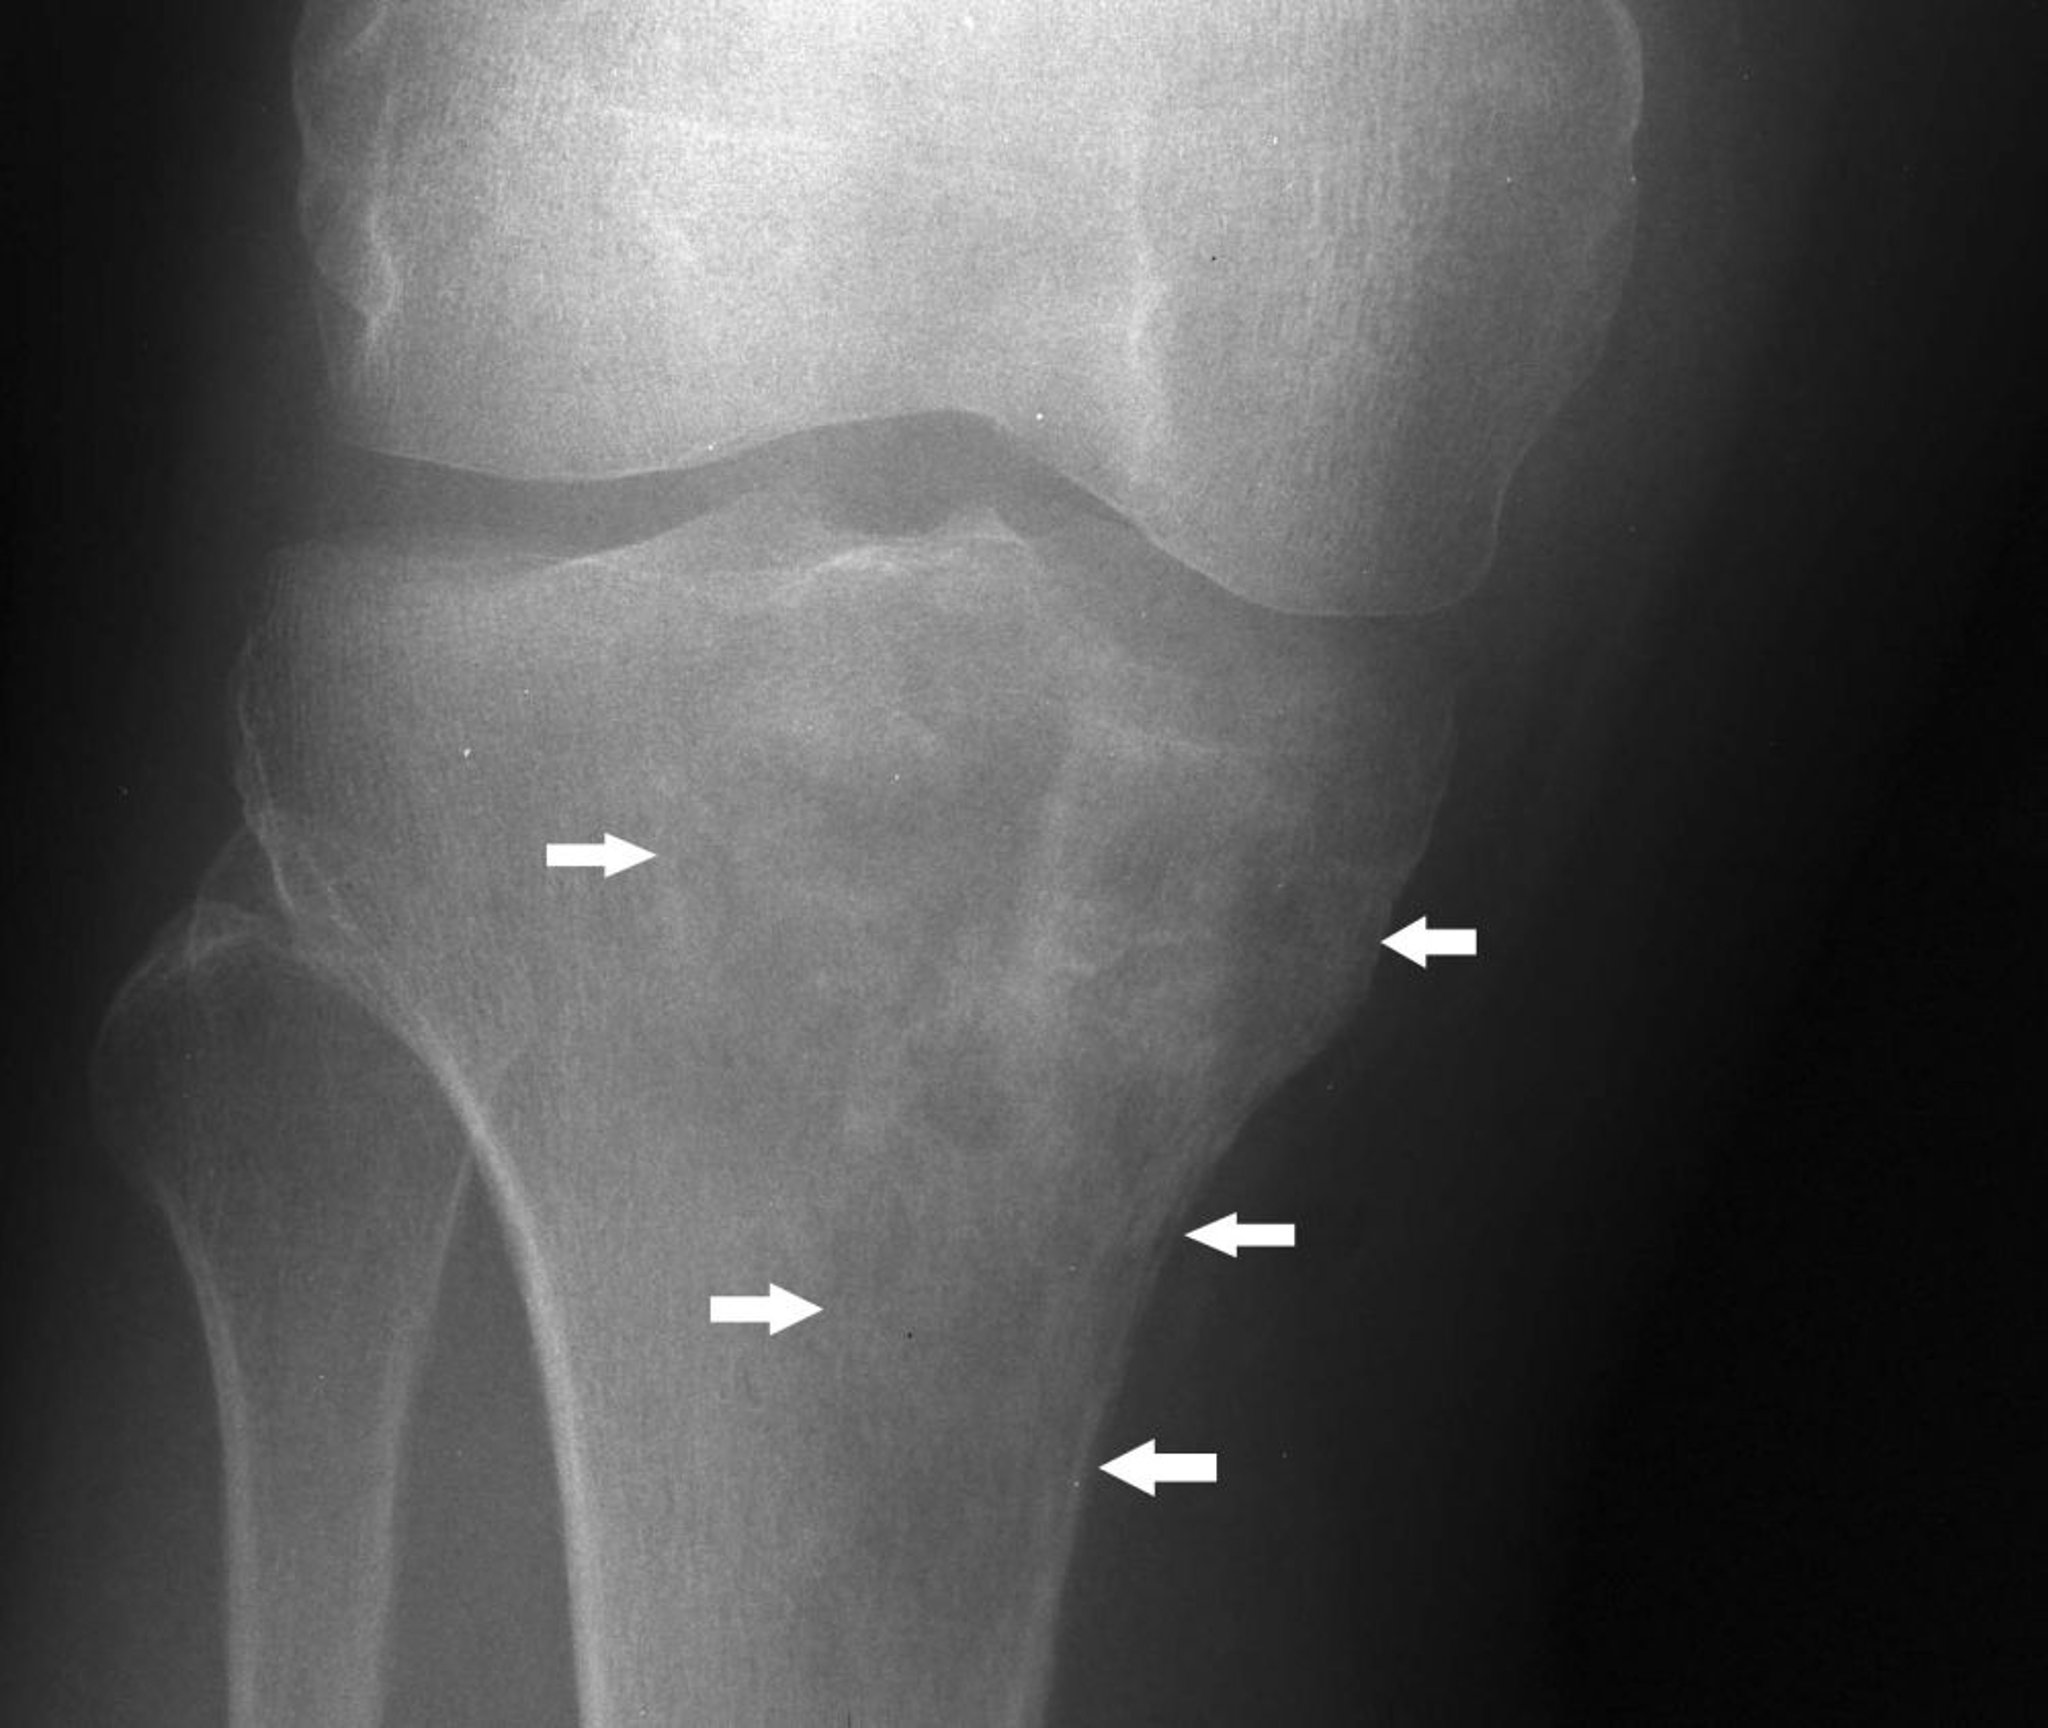

Phim chụp X-quang đầu gối này cho thấy u lympho ở xương chày gần với hình ảnh hỗn hợp của tình trạng tiêu xương và xơ cứng bên dưới lồi cầu xương chày trong (mũi tên).

Hình ảnh do bác sĩ Michael J. Joyce, và bác sĩ Hakan Ilaslan cung cấp.